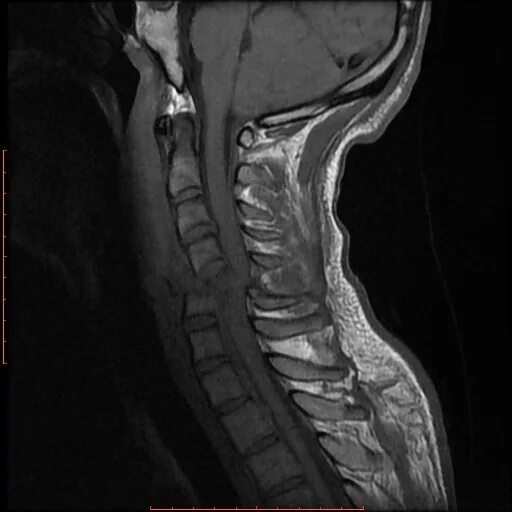

Мрт шейно поясничного отдела